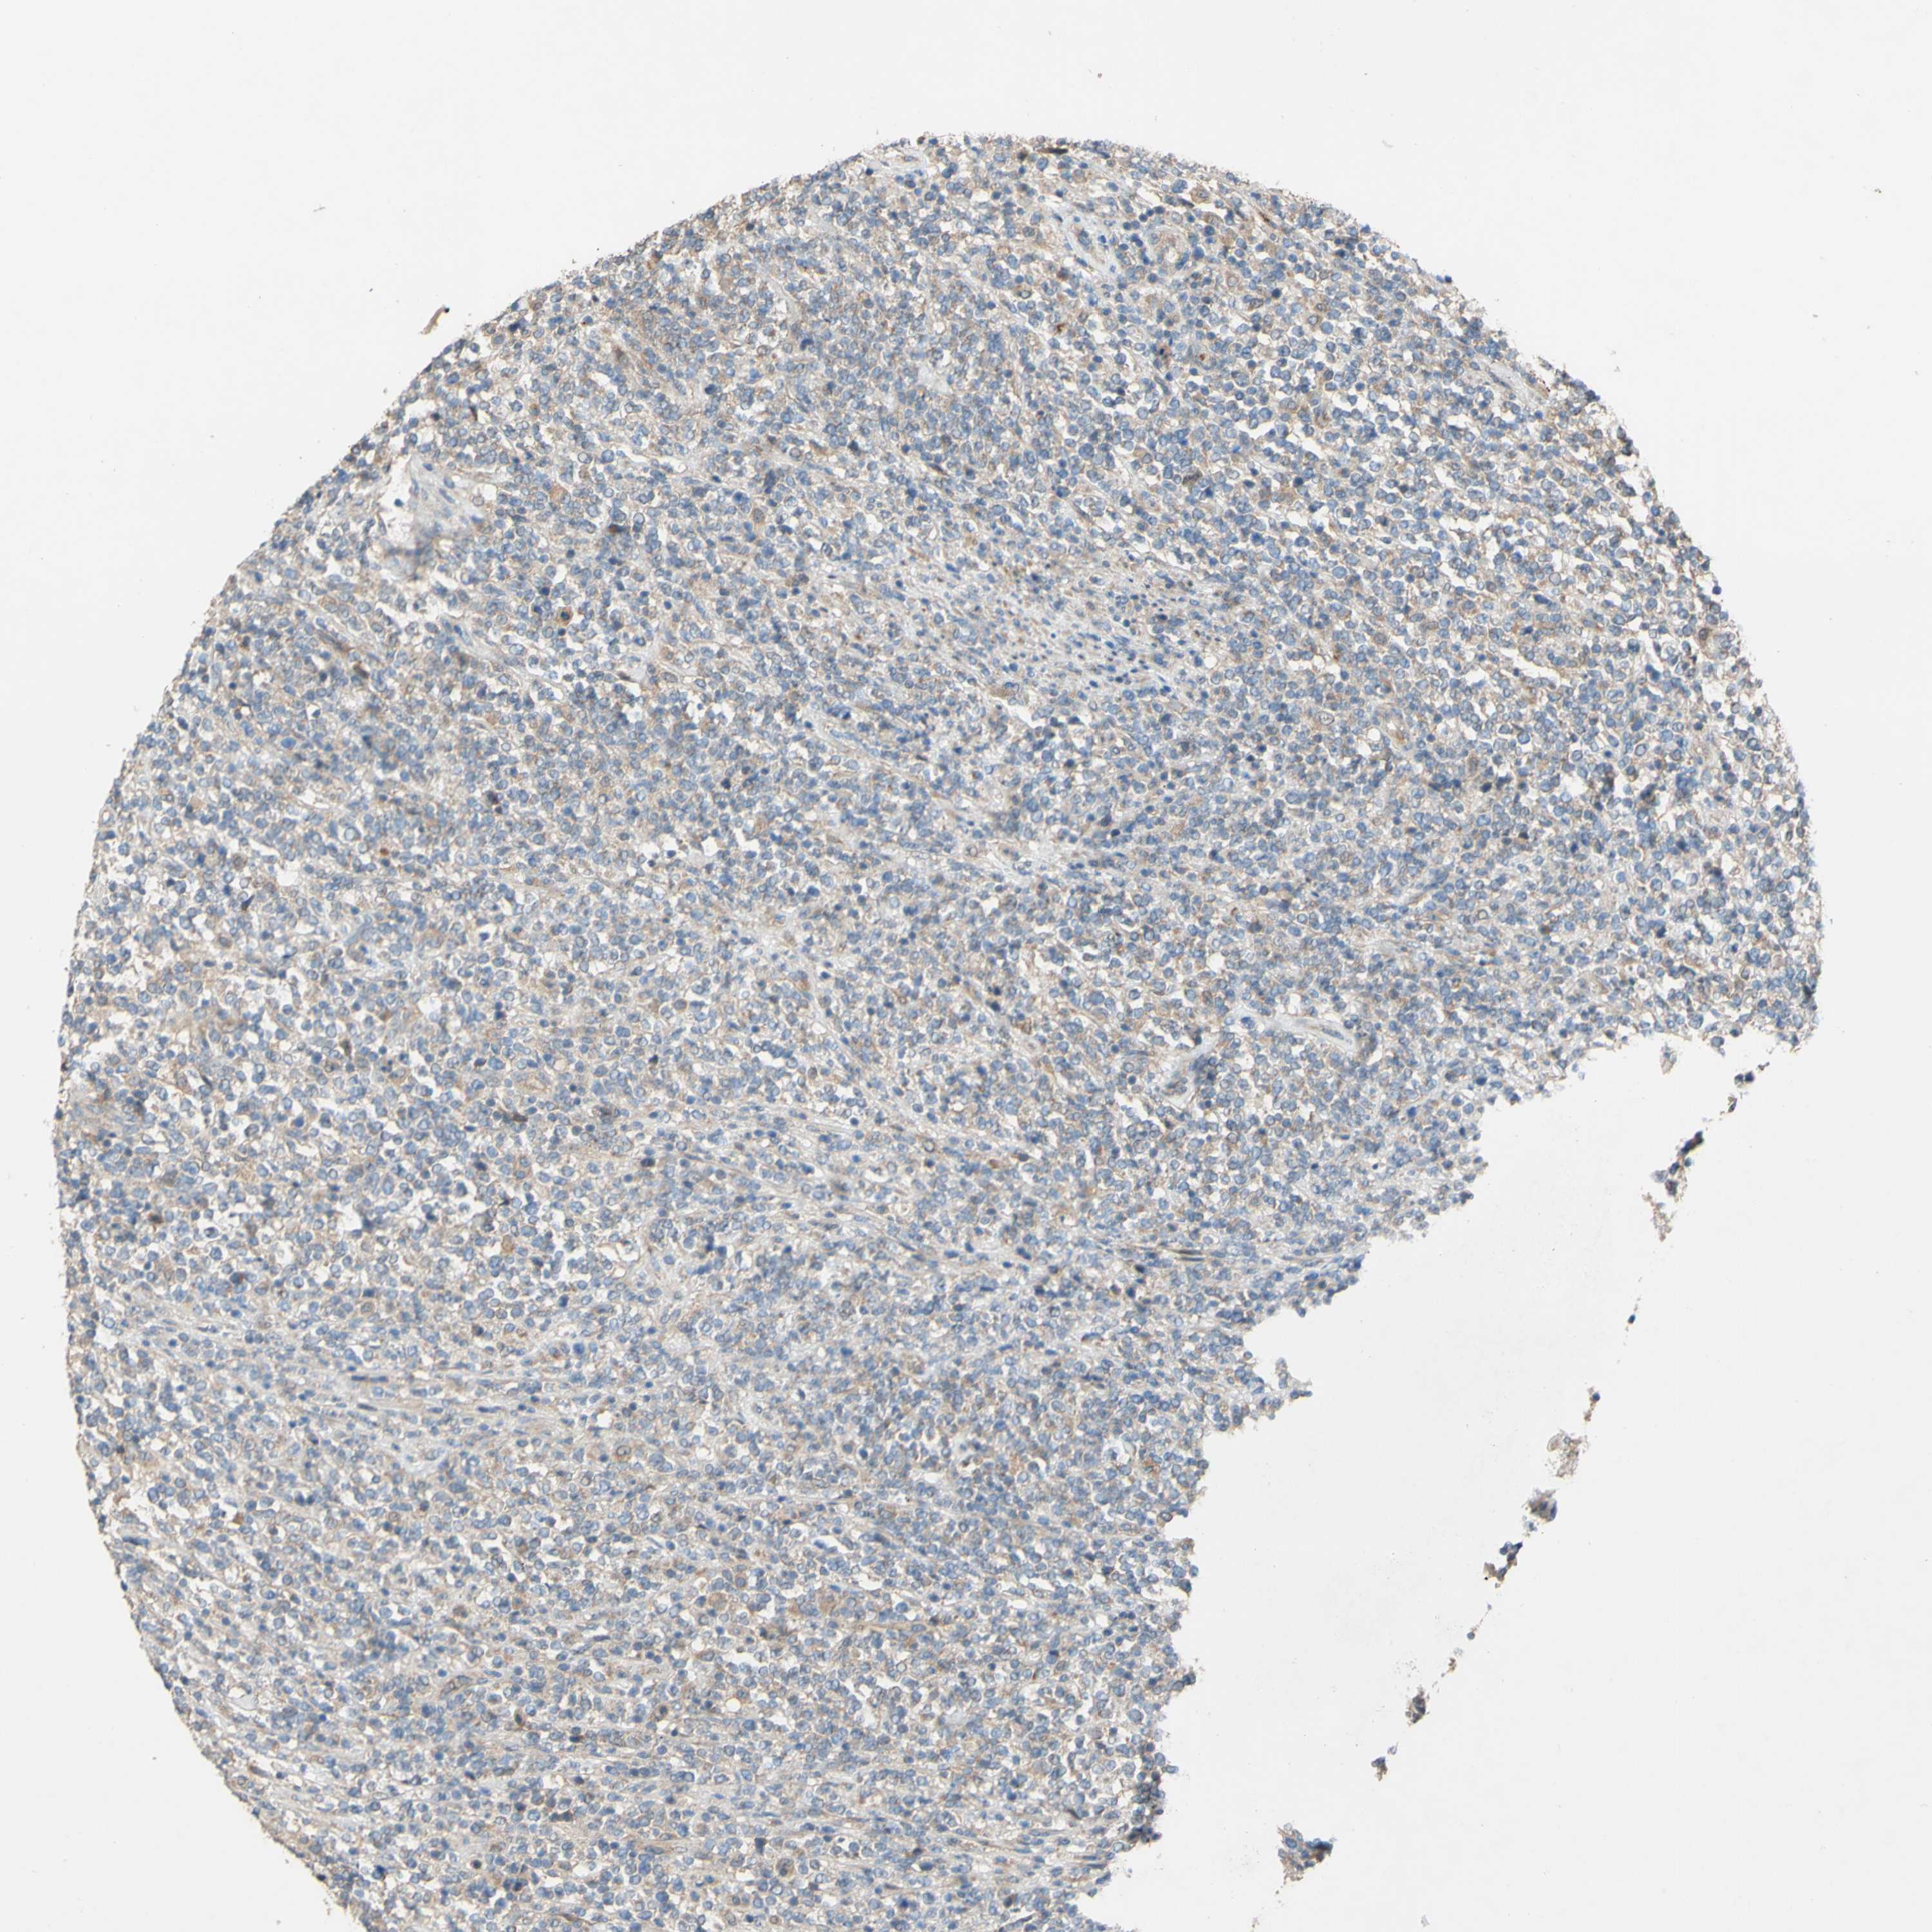

CANCER LYMPHOMA Show tissue menu

LYMPHOMA - Protein expressioni

A mouse-over function shows sample information and annotation data. Click on an image to view it in a full screen mode. Samples can be filtered based on level of antibody staining by selecting one or several of the following categories: high, medium, low and not detected. The assay and annotation is described here.

Antibody stainingi

Antibody staining in the annotated cell types in the current human tissue is reported as not detected, low, medium, or high, based on conventional immunohistochemistry profiling in selected tissues. This score is based on the combination of the staining intensity and fraction of stained cells.

Each image is clickable and will lead to virtual microscopy that enables deeper exploration of all samples and also displays staining intensity scores, fraction scores and subcellular localization as well as patient and tissue information for each sample.

Antibody HPA011868

Antibody CAB024949

Staining

High

Medium

Low

Not detected

Intensity

Strong

Moderate

Weak

Negative

Quantity

>75%

75%-25%

<25%

None

Location

Nuclear

Cytoplasmic/membranous

Cytoplasmic/membranous,nuclear

Hodgkin's disease, NOS

Malignant lymphoma, non-Hodgkin's type, High grade

Malignant lymphoma, non-Hodgkin's type, Low grade